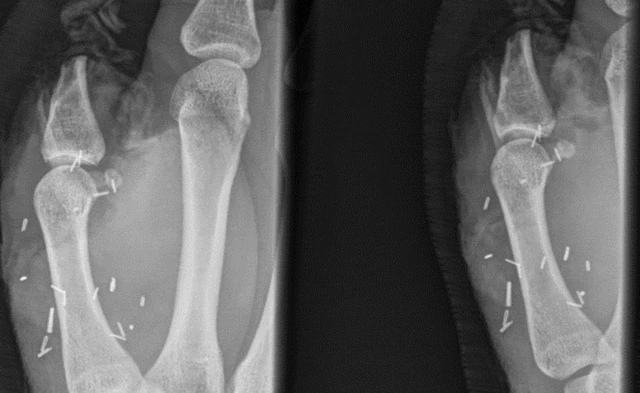

20-летний работник фермы Зак Митчелл пострадал от действий разбушевавшегося быка: хируги не смогли спасти большой палец на правой руке австралийца, поэтому воспользовались его аналогом на ноге в качестве замены.

Митчеллу пришлось за три месяца перенести две неудачные операции, в ходе которых врачи тщетно пытались вернуть его оторванную конечность на место.

Митчелл поначалу отнекивался и долго раздумывал, но потом согласился, и две недели назад в Сиднейской глазной больнице прошла редчайшая операция, которая длилась больше восьми часов.

В глазной больнице особо подчеркнули, что пересадка целого большого пальца - крайне нестандартная практика на данный момент, однако трансплантации его фрагментов уже вошли в повседневностть пластической хирургии.